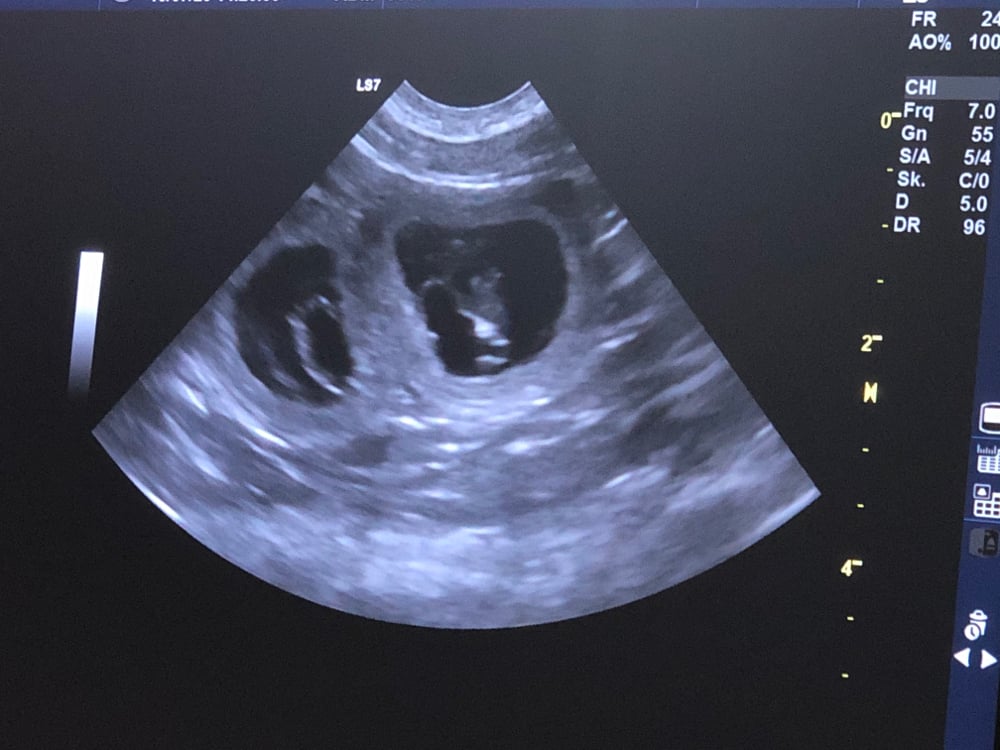

10.7.20 Hurra es hat geklappt die Tierärztin konnte auf dem Ultraschall Bild schon 6 Föten sehen, wir freuen uns riesig dass Paige Welpen erwartet.